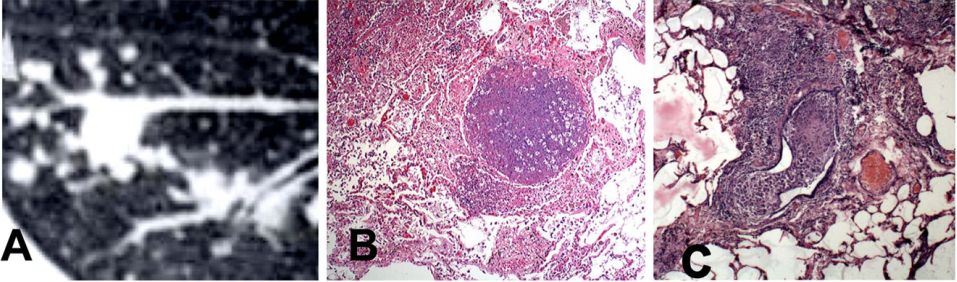

支气管内结核引起支气管阻塞是继发性结核在病理及影像学上的常见表现。最早的放射学特征是CAT扫描上的“树芽”征,如图3所示。感染的细胞和碎片填满小支气管,产生可见的“树状枝成分”。相邻肺泡的病灶充满了泡沫状肺泡巨噬细胞和脂质碎片,形成“树芽成分”。肺泡巨噬细胞逐渐形成泡沫并退化,在肺泡内可见脂质碎片,有时罕见抗酸杆菌。这在x光片上产生磨砂玻璃外观。这些病变可能在一年或更长时间内缓慢进展,很少或没有临床疾病。

图3.继发性肺结核的支气管闭塞。树芽型是早期原发性肺结核的典型CT表现(A)。X光片上的树枝是充满受感染细胞和碎片的支气管,而芽是肺泡中结核性肺炎的区域。切片(B, C)显示支气管被这种碎片阻塞。支气管阻塞已被许多作者报告在100%的继发性肺结核病例中(H & E染色100×放大倍数)。